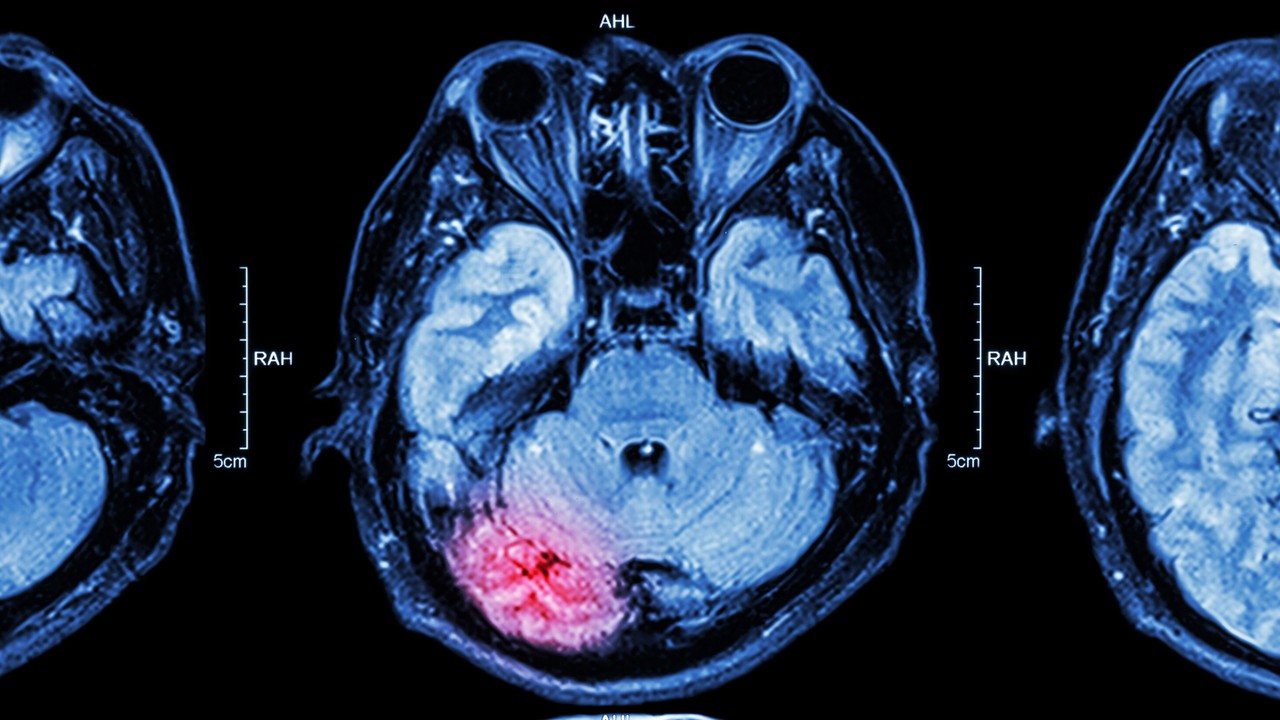

Bóle pleców są prawdziwą chorobą cywilizacyjną. Często leczenie wiąże się z wizytą u ortopedy lub — coraz popularniejszych, między innymi za sprawą filmików w internecie pokazujących rzekomo udane zabiegi — chiropraktyków. Nastawienie przemieszczonego kręgu może przynieść pacjentom niemal natychmiastową ulgę, jednak właśnie podczas tego zabiegu czai się ukryte niebezpieczeństwo: udar mózgu spowodowany przez samą procedurę, która ma uwolnić od bólu. Doświadczony fizjoterapeuta wyjaśnia, jak można zminimalizować to ryzyko. Przestrzega też, że największą grupą ryzyka są raczej młodsi pacjenci, czyli poniżej 45. roku życia. — W tej grupie wiekowej jest to nawet najczęstsza przyczyna udaru — mówi.